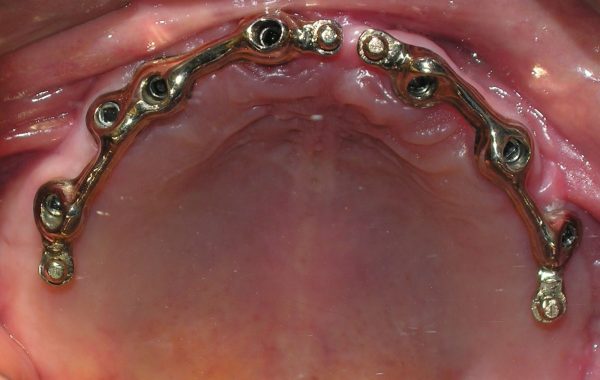

Se unieron estos implantes por medio de dos barras de oro, para soportar la dentadura y darle mayor retención.

caso 5-3

Barras de oro colocadas sobre los implantes